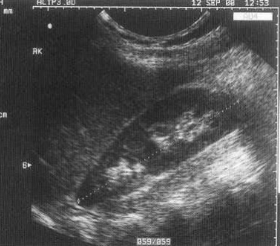

Double Collecting System (aka Duplex Kidney)

Duplication of collecting system - may be complete (2 ureters) or incomplete (1 ureter).

image of duplex kidney

sonographically of duplex kidney

Band of cortical tissue seen throughout a mid area section of the kidney that can be seen in both long and trans.